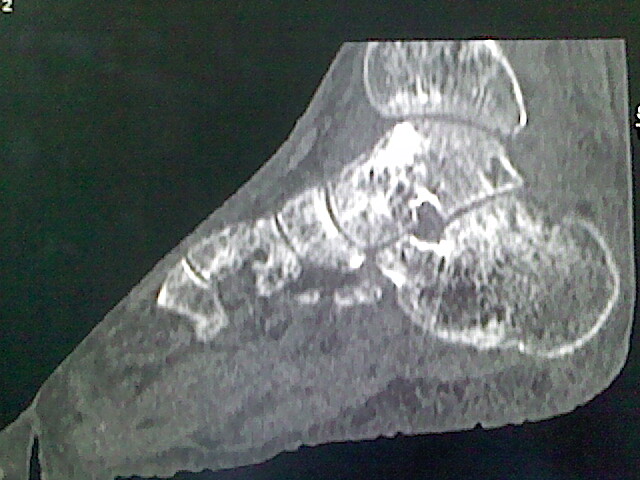

标题: CT16814:男,76岁,左小腿疼痛,不能站立 大家给看看 [打印本页]

男,76岁,左小腿疼痛,不能站立

本例骨质改变主要表现为滑膜或韧带区的骨侵蚀融解(胫腓联合区骨质破坏无硬化边),距骨后部骨质破坏区有硬化边及死骨样改变.所以,本例考虑关节结核可能性大,绒毛膜结节性滑膜炎多发于中年,且极少见于膝髋以外的关节,骨质硬坏也以压陷吸收为主,有明显的硬化边,骨膜增生呈结节状(可以mr鉴别),所以本例暂除外.

另不除外可引起相似表现的其他炎症如布氏杆菌性关节炎等